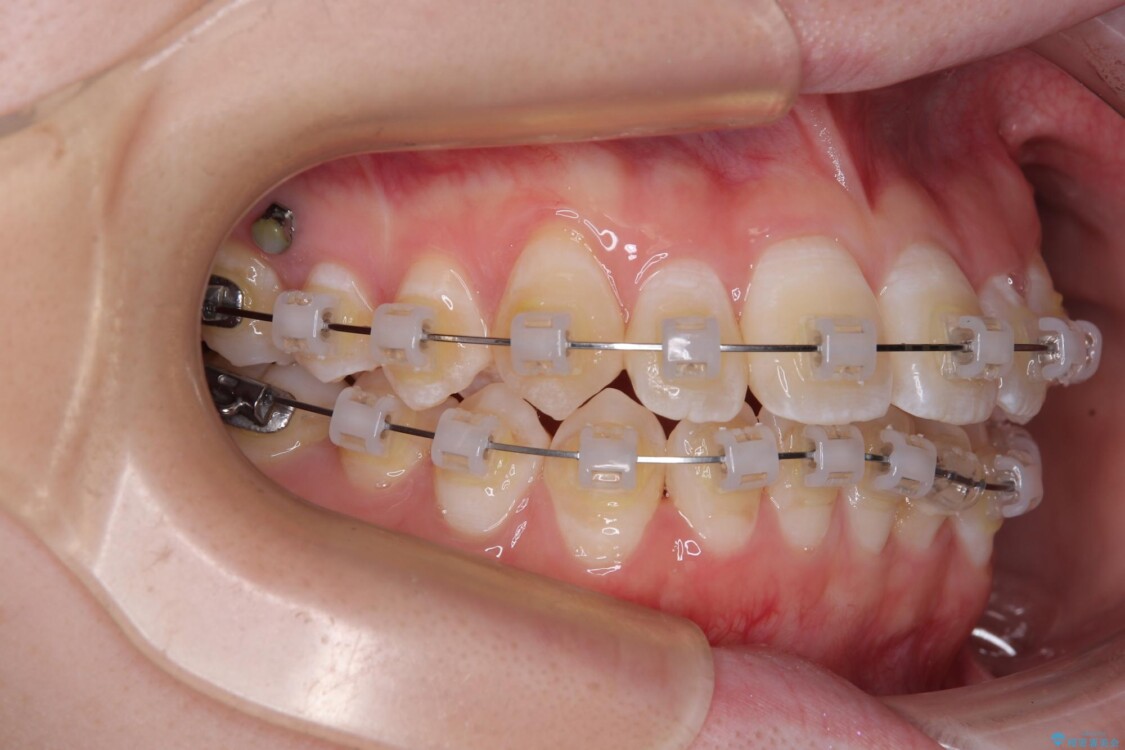

目立ちにくさと費用のバランスを考慮し、プラスチックブラケット+メタルワイヤーを採用。日常生活でも装置の存在感を気にせずお過ごしいただけます。

患者様の協力もあり、およそ1年間で治療を完了。スムーズな歯の移動を実現しました。

治療途中

• 【モニター】前歯のデコボコをスッキリ解消!目立ちにくいワイヤー矯正でスピーディに治療完了 治療途中画像